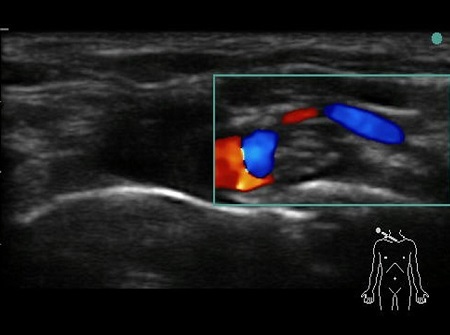

- The first structure to locate is the round pulsating hypoechoic subclavian artery (A), lying on top of the hyperechoic first rib (R). Use Doppler to assess for vessels. See Fig. 2.

Fig. 2. Bidirectional Doppler used here to highlight the subclavian artery.

Hypoechoic vessels may be seen among the brachial plexus nerves (also round hypoechoic structures). Because they have similar appearance, it is important to differentiate them (colour Doppler MUST be used) (16). See Fig. 9.

Fig. 9. Doppler highlighting subclavian artery with dorsal scapular artery passing posteriorly through brachial plexus.